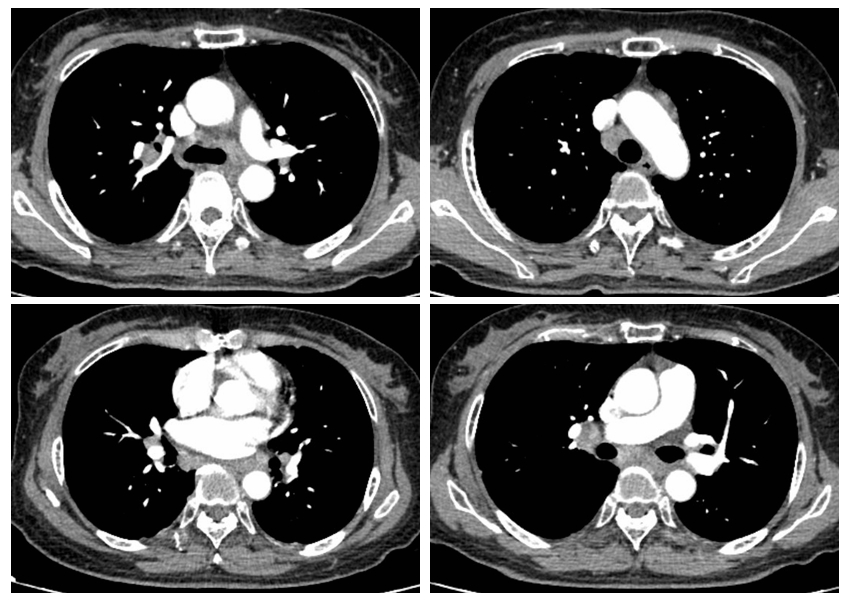

结节病是一种原因不明的系统性肉芽肿性疾病,损害部位以肺部和胸内淋巴结最常见,也包括皮肤、眼睛、关节、神经系统、心脏和全身其他部位。大约1/3患者可有非特异性症状,如干咳、发热、乏力、体重下降、关节痛等。其他症状还包括皮疹、视物模糊、心律不齐、肌肉或骨骼疼痛等。结节病的胸部影像学最典型表现是肺门和纵隔对称性的淋巴结肿大,需要与肺结核、肺恶性肿瘤的淋巴结转移、淋巴瘤等疾病相鉴别。